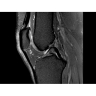

• РЧ-катушки, оптимизированные для исследования конкретных участков тела — элементы катушек высокой плотности располагаются вокруг исследуемых участков тела и при необходимости обеспечивают расширенный охват и оптимальное качество изображений при каждой процедуре.

• Радиологам достаются изображения великолепного качества, необходимые им для постановки точных диагнозов.